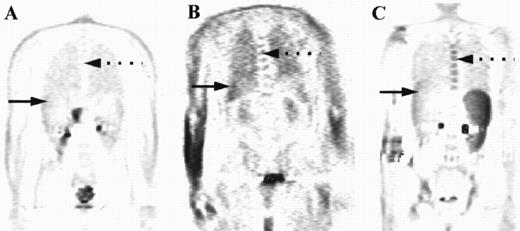

For the purposes of this study, the intensity and distribution of FDG activity within the marrow was visually scored by three nuclear medicine physicians independently. The marrow was assumed to be abnormal where the uptake was equal to or greater than uptake into the liver, provided the liver uptake was greater than background. In one patient where there was negligible uptake within the liver, marrow uptake was compared to uptake within soft tissue rather than using the liver as the reference organ. The pattern of increased uptake was also noted, with patients who appeared to have focal disease only within the marrow differentiated from those with diffusely abnormal marrow changes. Representative examples of cases with marrow uptake of differing intensity (Fig 1) and distribution (Fig 2) are shown.

Coronal images are shown from three patients with different degrees of marrow uptake on PET. FDG uptake within the marrow is seen on these sections in the thoracic spine (broken arrows) and within the liver (solid arrow). The intensity of uptake was graded as less than liver (A), equal to liver (B), or greater than liver (C), with the marrow deemed to be abnormal where uptake was equal to or greater than liver.